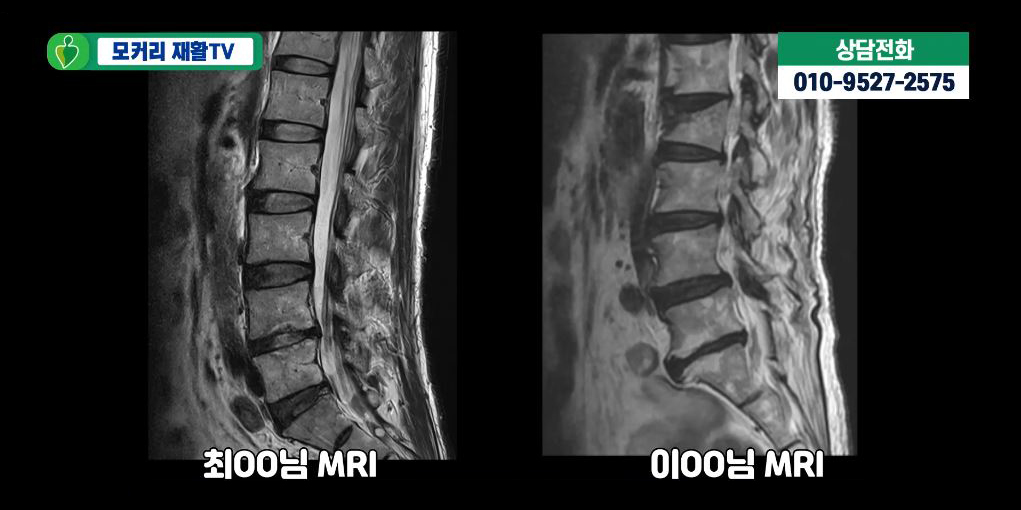

- MRI 검사: 척추관의 좁아짐, 디스크 돌출, 신경 압박 정도를 정확히 볼 수 있습니다. (가장 정확한 검사)